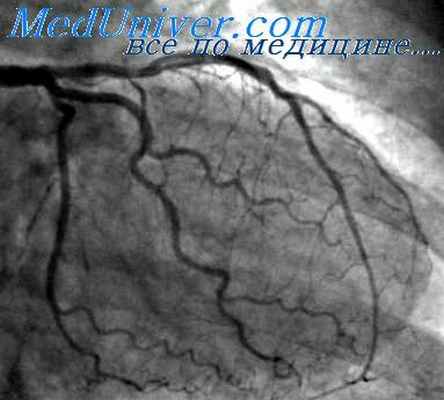

Исследование сосудов сердца. Проводится через прокол на руке. Продолжительность диагностики около 20 минут.

Исследование сосудов сердца на рентгеновской установке с введением контраста. Используется доступ на бедре. После исследования пункционное отверстие закрывается специальным сшивающим устройством.